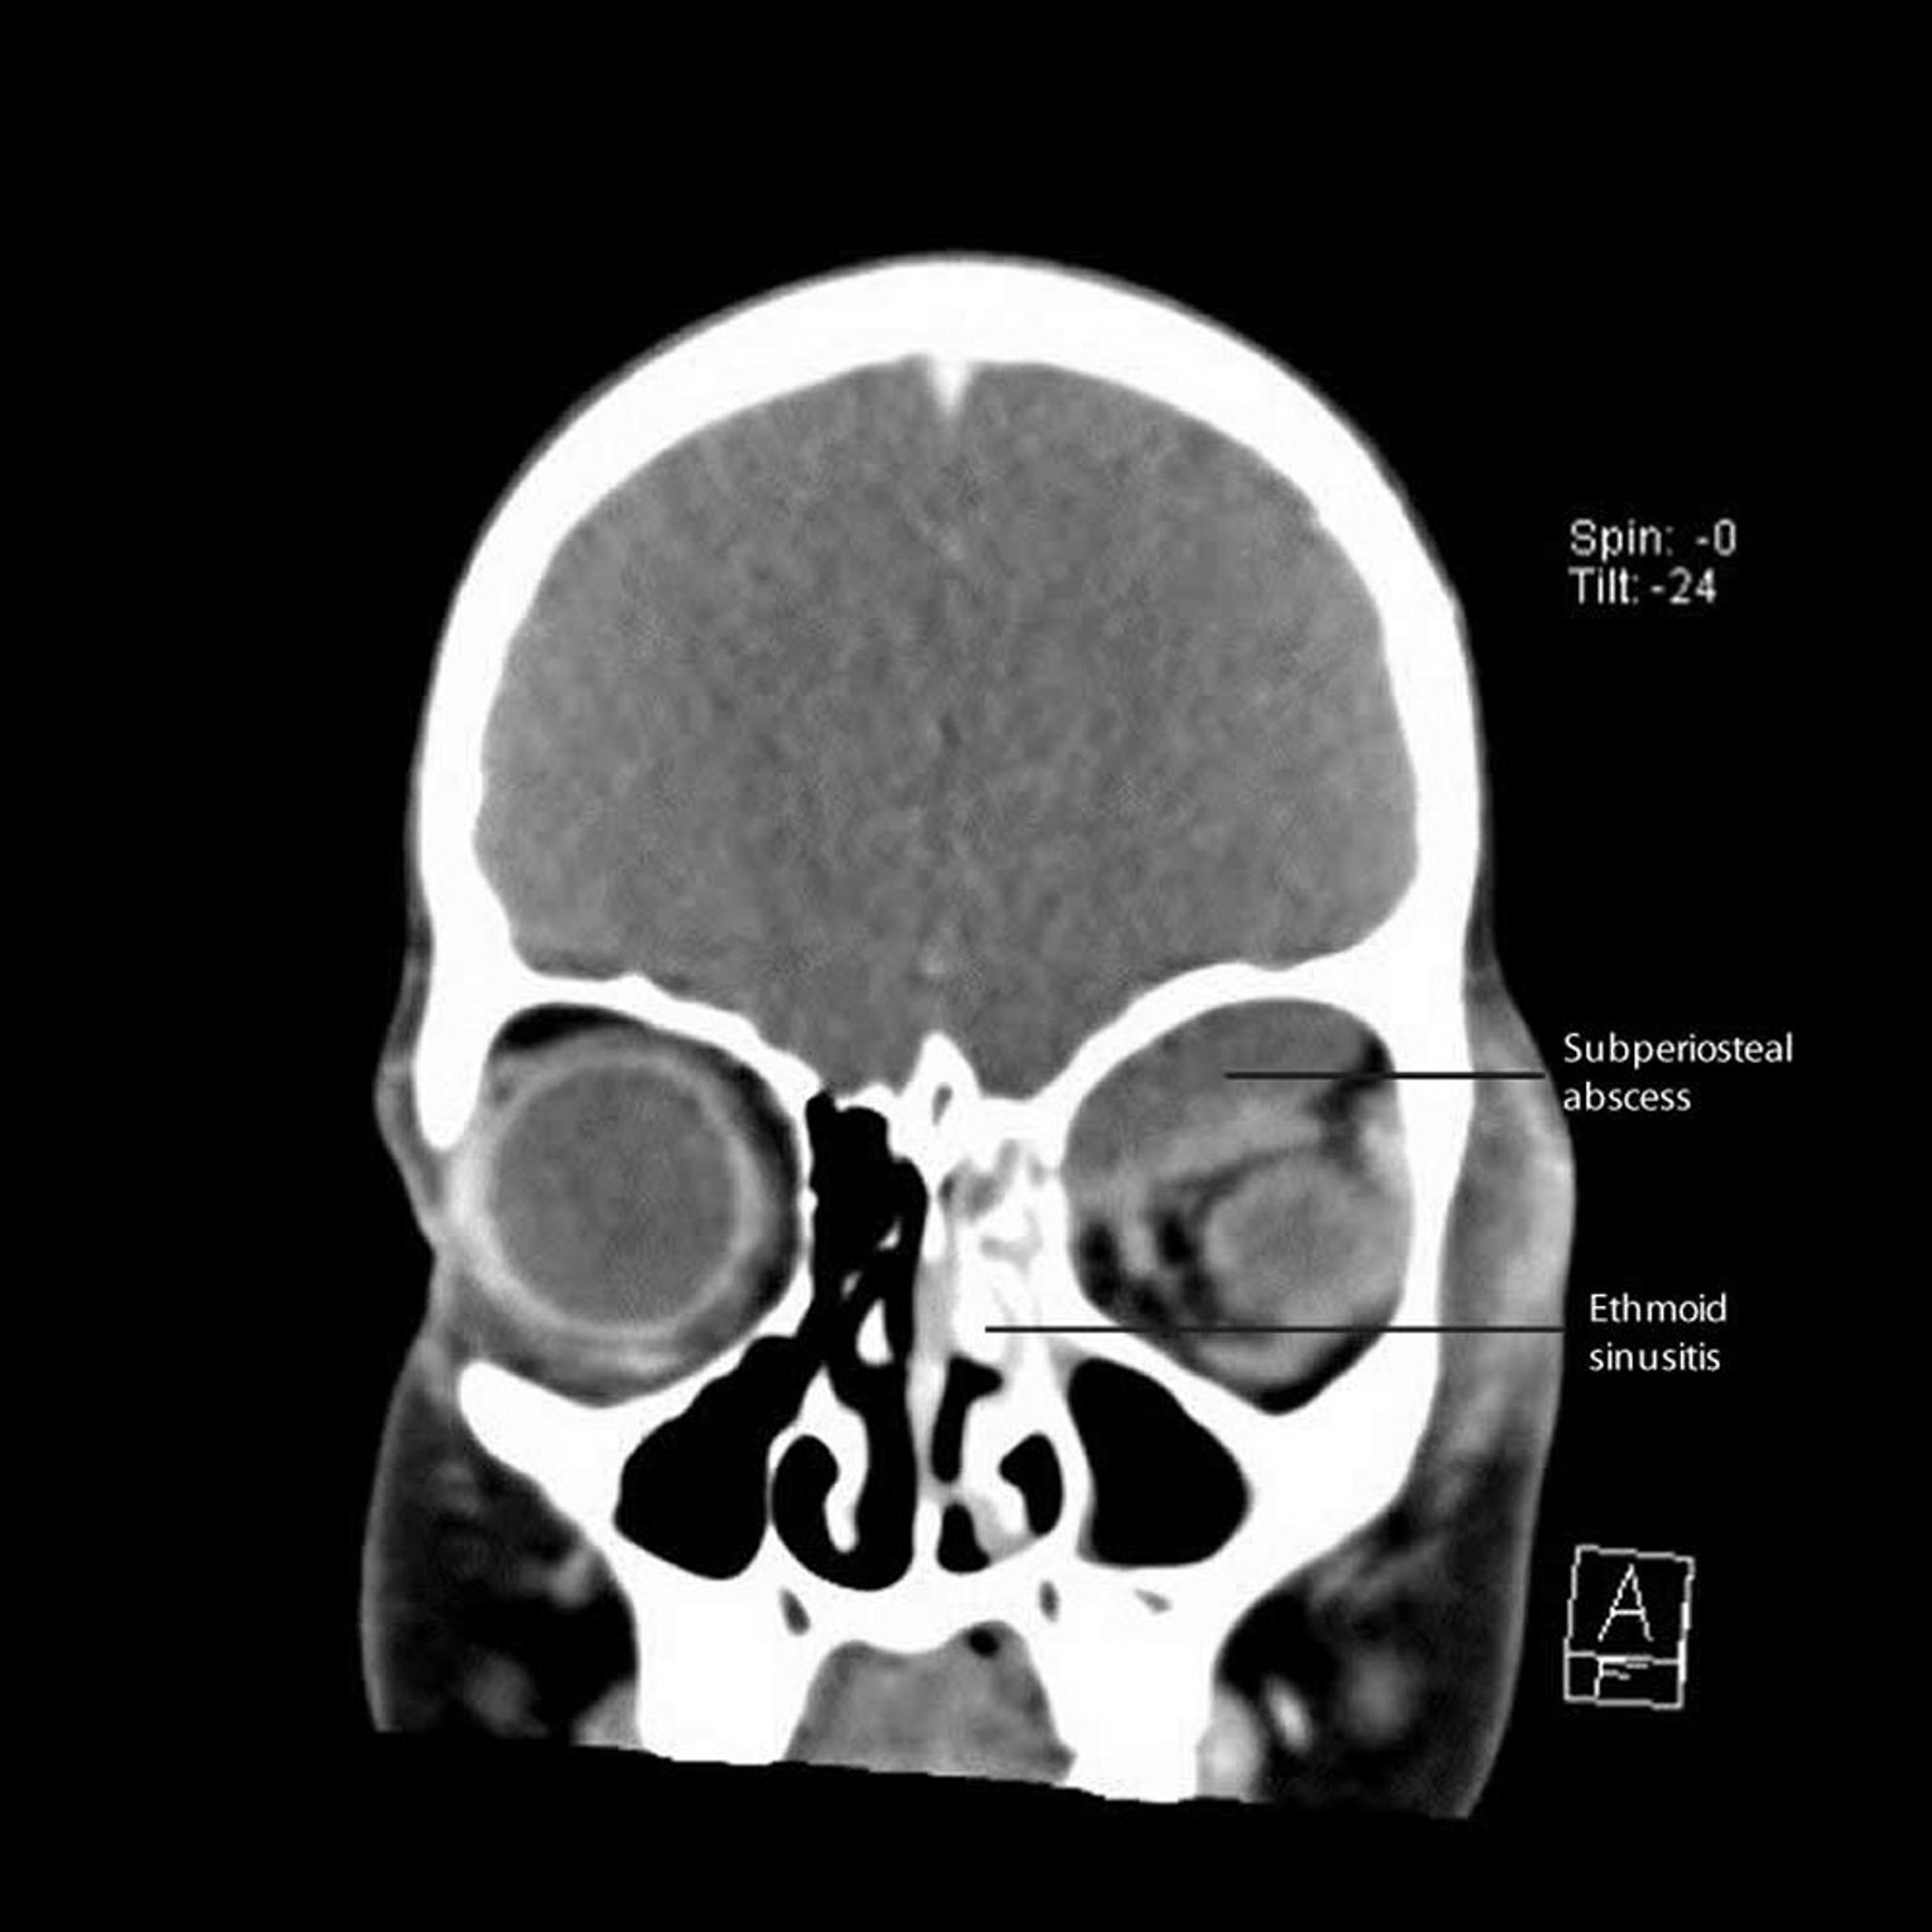

骨膜下膿瘍を伴う篩骨洞炎

このCT画像には,眼窩の内側壁および上壁に沿って生じ,近傍に骨膜下膿瘍を伴った左側の篩骨洞炎が写っている。

CT courtesy of James Garrity, MD.